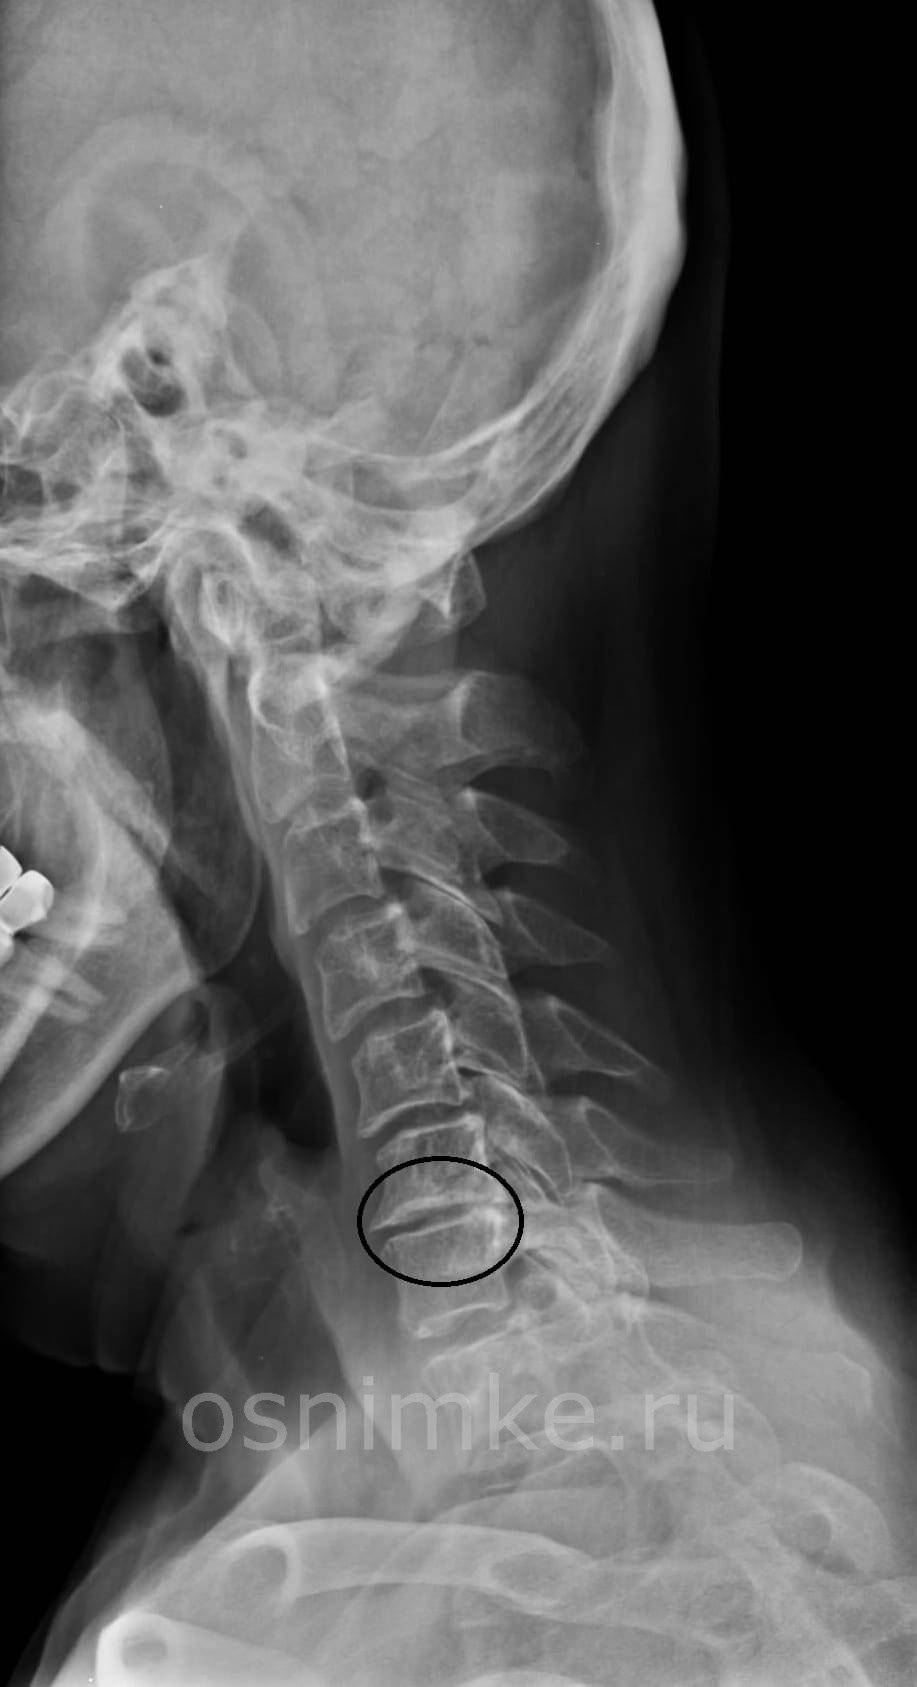

Остеохондроз шейного отдела

Получив результаты исследования, врач внимательно изучает, что показал рентген шейного отдела позвоночника. По результатам снимков можно увидеть отклонения или особенности в этом отделе:

- последствия травматического повреждения позвоночного столба в области шеи. Это могут быть вывихи, ушибы, смещения, трещины;

- трансформация позвоночника в области шеи;

- наросты, образовывающиеся вокруг позвоночной артерии в районе первого шейного позвонка — это аномалия Киммерле. Эта патология является врождённой, поэтому диагностировать её можно даже у маленьких детей. При сдавливании позвоночной артерии происходит нарушение кровоснабжения;

- дегенеративно-дистрофические изменения, например, шейный остеохондроз;

- воспалительные патологии, провоцирующие раздражение межпозвонкового нерва. Это состояние провоцирует шейный радикулит;

- наличие аномального костного образования, например, клиновидного позвонка;

- искривление позвонков из-за разрастания костной ткани. К таким патологиям относится спондилез;

- остеопороз в шейном отделе позвоночника;

- обменные нарушения;

- кифоз в шейно-грудном сегменте;

- опухоли, локализованные в шейном отделе;

- грыжи и протрузии дисков.